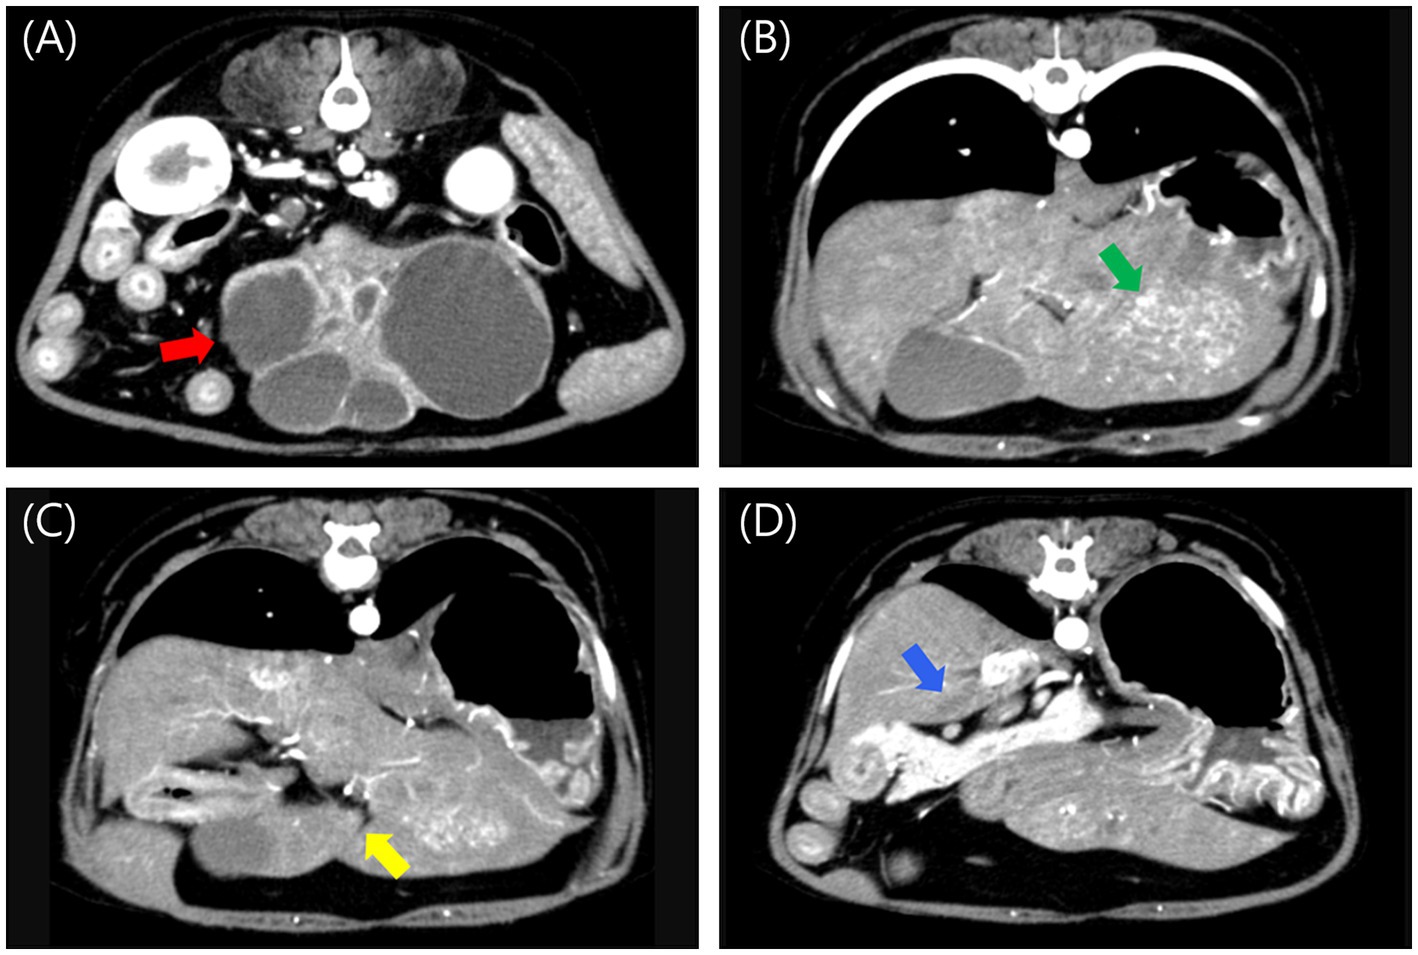

Abdominal radiography revealed a relatively well-defined soft tissue opacity mass with a round-to-amorphous shape in the mid-abdomen. Abdominal ultrasound identified a multicystic, amorphous-shaped mass measuring approximately 7 cm in diameter, most likely arising from the left lateral hepatic lobe. A heterogenous, round-shaped mass approximately 2.5 cm in diameter with significant blood flow was also detected, likely in the left medial lobe. Triphasic computed tomography (CT) imaging (Hi Speed QX/I, GE Medical Co., Milwaukee, WI, USA), which had been performed at a local hospital prior to referral, identified multiple hepatic masses. A heterogeneous, amorphous, pedunculated mass (#1) originating from the left lateral lobe measured 7.29 × 4.37 × 4.06 cm (W × H × L) and exhibited contrast enhancement in the arterial, portal, and delayed phases, with rapid washout observed in the delayed phase. The mass contained at least six well-defined non-enhancing cystic lesions. A heterogeneous mass (#2) in the left medial lobe measuring 3.12 × 2.02 × 2.97 cm (W × H × L) was contrast-enhancing in the arterial and portal phases but non-enhancing in the delayed phase. An ill-defined, non-enhancing nodule measuring approximately 2 mm was also identified in the left lateral lobe. A mass (#3) in the quadrate lobe measuring 0.84 × 0.71 × 0.73 cm (W × H × L) was isoattenuating and demonstrated contrast enhancement in the arterial and portal phases but not in the delayed phase. A mass (#4) in the caudate process of the caudate lobe measuring 0.92 × 0.36 × 0.66 cm (W × H × L) was isoattenuating and non-enhancing in all phases (Figure 1).

Figure 1. Post-contrast arterial phase computed tomography images of multiple liver masses. (A) A large, amorphous, pedunculated, contrast-enhancing mass (#1, red arrow) with internal cavitations originating from the left lateral lobe, measuring 7.29 × 4.37 × 4.06 cm (W × H × L). (B) A heterogeneous, contrast-enhancing mass (#2, green arrow) in the left medial lobe, measuring 3.12 × 2.02 × 2.97 cm (W × H × L). (C) An isoattenuating, contrast-enhancing mass (#3, yellow arrow) in the quadrate lobe, measuring 0.84 × 0.71 × 0.73 cm (W × H × L). (D) An isoattenuating, non-enhancing mass (#4, blue arrow) in the caudate process of the caudate lobe, measuring 0.92 × 0.36 × 0.66 cm (W × H × L). W, width; H, height; L, Length.